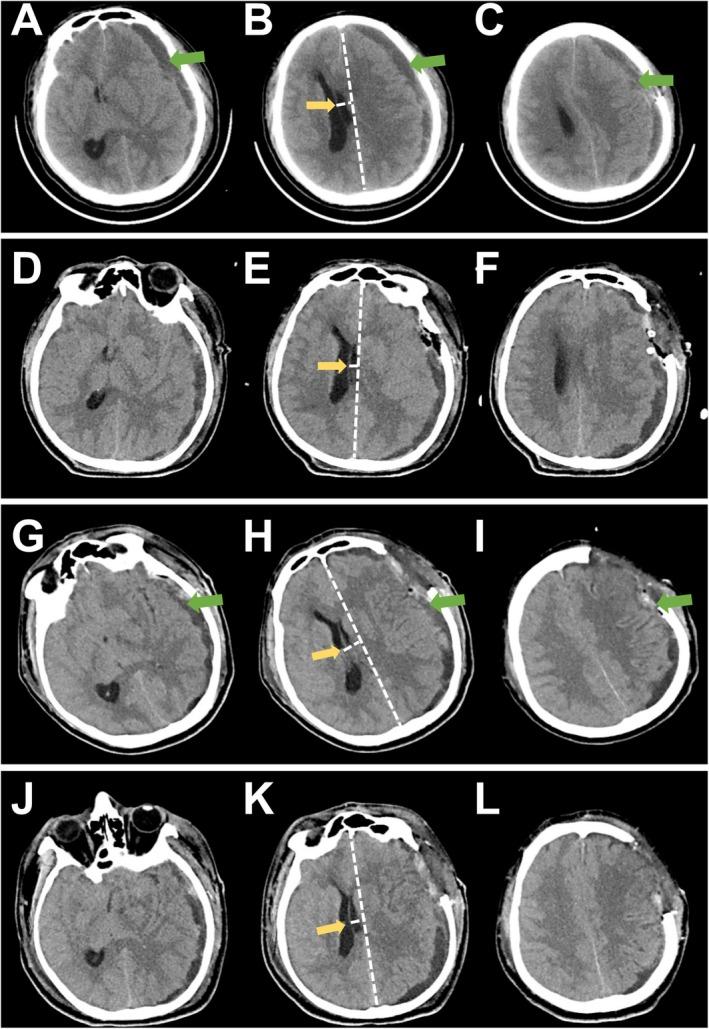

Recurrent Subdural Hematoma: A Case Report of Diagnostic Pitfall of Spontaneous Intracranial Hypotension and Successful Management With Targeted Epidural Blood Patch.

Spontaneous intracranial hypotension should be considered in subdural hematoma cases without cerebral trauma or underlying disease, particularly among non-elderly patients. Targeted epidural blood patch is recommended as a first-line intervention prior to surgical management in cases of spontaneous intracranial hypotension-induced subdural hematoma.